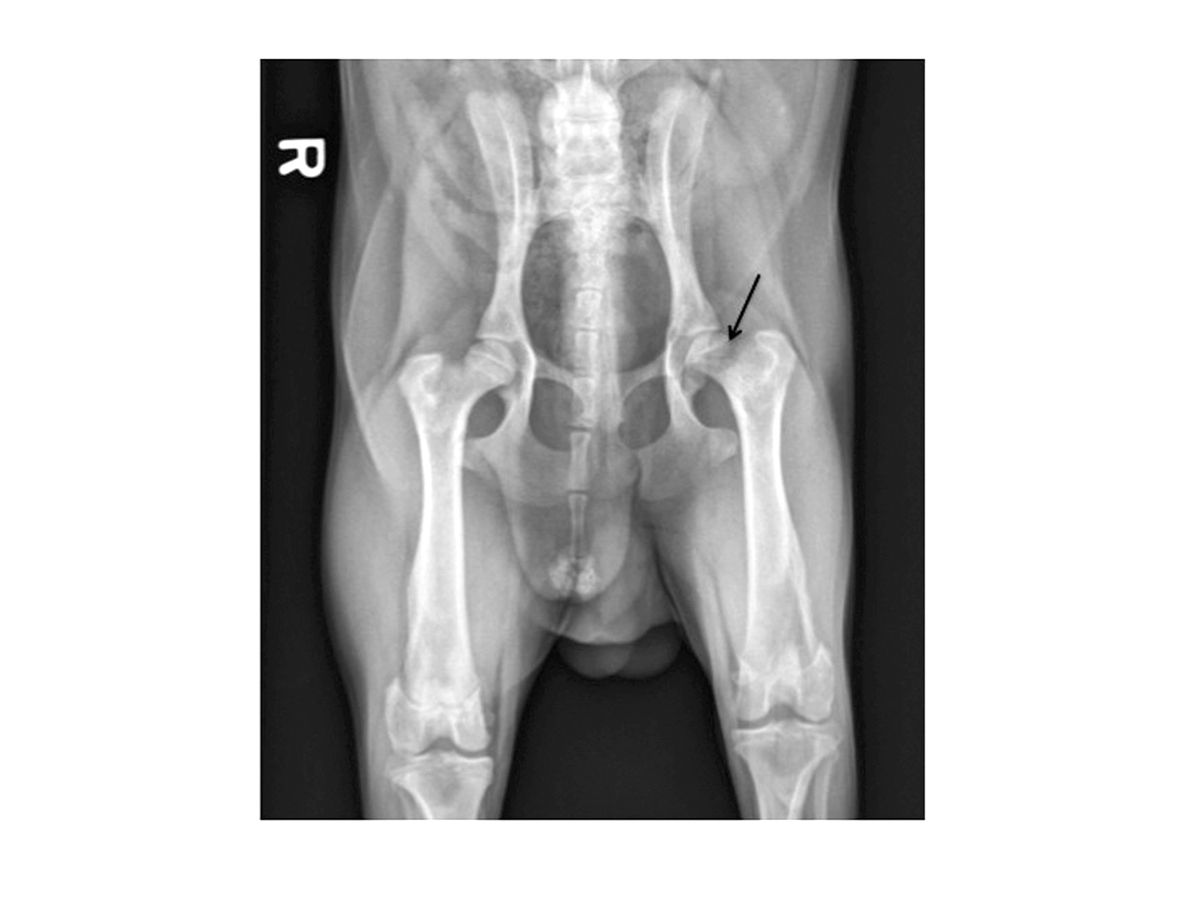

Although the clinical exam findings, along with a typical signalment, are highly suggestive of LCPD, radiographs are usually obtained as supporting evidence for LCPD. Initially areas of lysis and demineralization may be present in the subchondral region of the femoral head and neck (Figure 1). As the condition progresses, obvious collapse of the femoral head and neck may be apparent (Figure 2). Later in the course of the disease, evidence of re-mineraliz- ation and bone healing may be present. Secondary osteo- arthritic changes may be seen, including formation of osteophytes (especially along the dorsal acetabular rim and femoral head) and flattening of the femoral head.

A radiograph of a dog showing typical early changes of LCPD. The arrow denotes areas of early demineralization.

Figure 1. A radiograph of a dog showing typical early changes of LCPD. The arrow denotes areas of early demineralization.© Darryl L. Millis